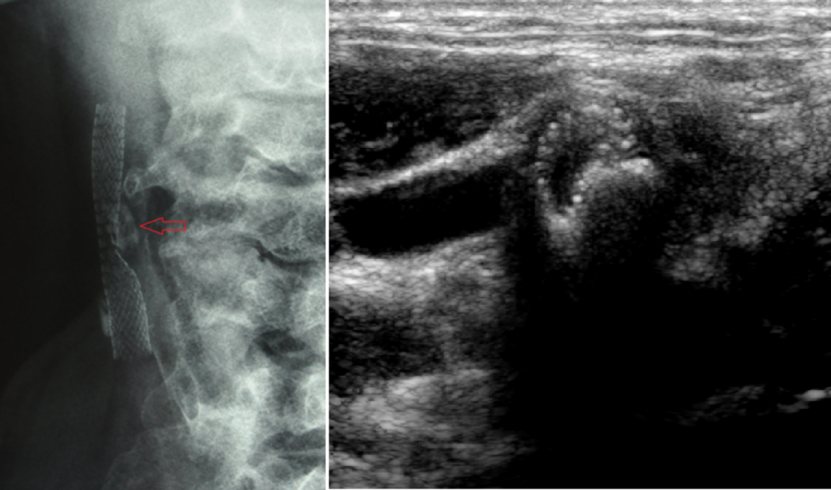

术前应常规进行高分辨率MRI管壁成像、CTA颈动脉三维重建、超声斑块回声评估等,综合判断斑块稳定性、钙化分布、溃疡形态等,为手术策略提供依据。

图:病变性质-严重钙化